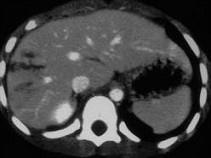

问题 下列图像最佳诊断是 ( )

选项 A、小肠破裂 B、胰腺损伤 C、结肠破裂 D、肝破裂 E、脾破裂

答案 D